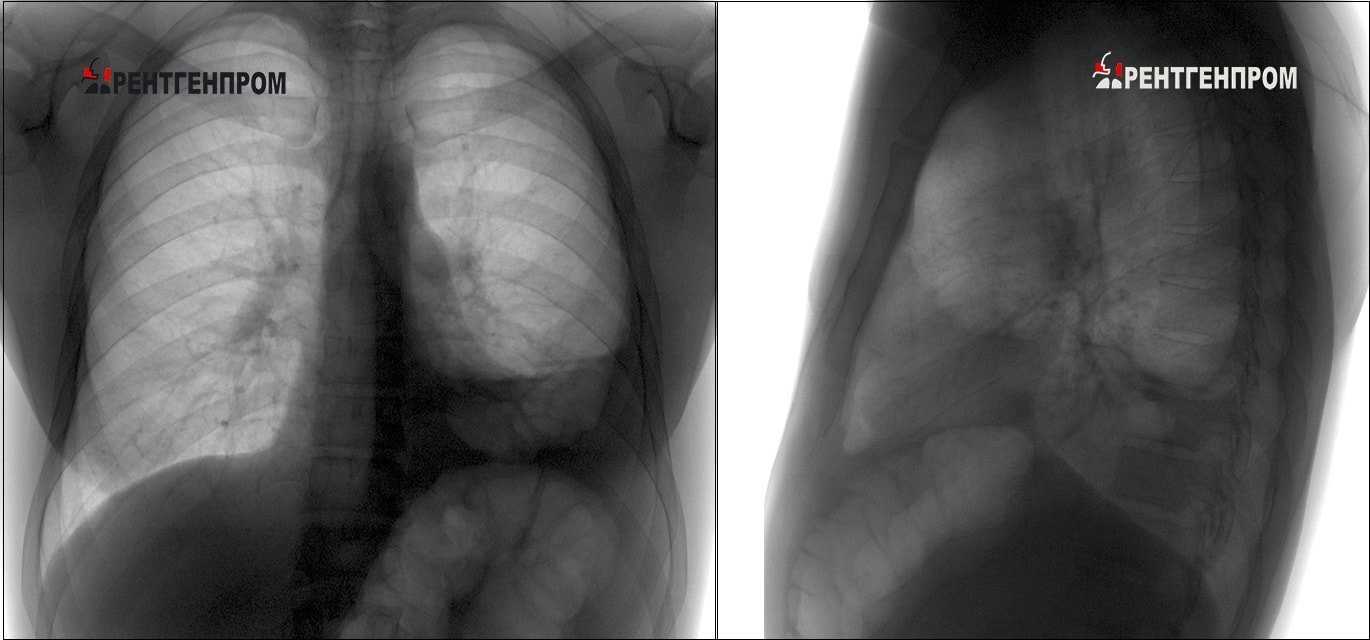

Как выглядит классический рентгеновский снимок лёгких

Классический рентгеновский снимок лёгких

Лёгкие человека выглядят на снимке таким образом: правое и левое лёгкой по сторонам от позвоночника, тень от сердца, ключицы, рёбра, купол диафрагмы. Расшифровкой полученных изображений занимаются специалисты, которые оценивают состояние лёгких пациента по следующей схеме:

- как лёгкие расположены в грудной клетке относительно других органов;

- количество лёгочных долей;

- форма парного органа и его размеры;

- лёгочный рисунок.

Лёгочная ткань здорового человека имеют однородную и равномерную структуру. В ряде случаев на рентгеновских снимках появляются пятна тёмной или светлой окраски. Это может свидетельствовать как о наличии серьёзных патологий, так и о физиологических процессах в лёгких, не являющихся отклонением от нормы. Однако, получив такой снимок, пациент с беспокойством начинает искать информацию о значении затемнений или светлых кругов на снимке. Далее будет рассказано о том, что они означают.

Билатеральное нижнее затемнение в легких (слева больше, чем справа) и небольшое нарушение прозрачности слева